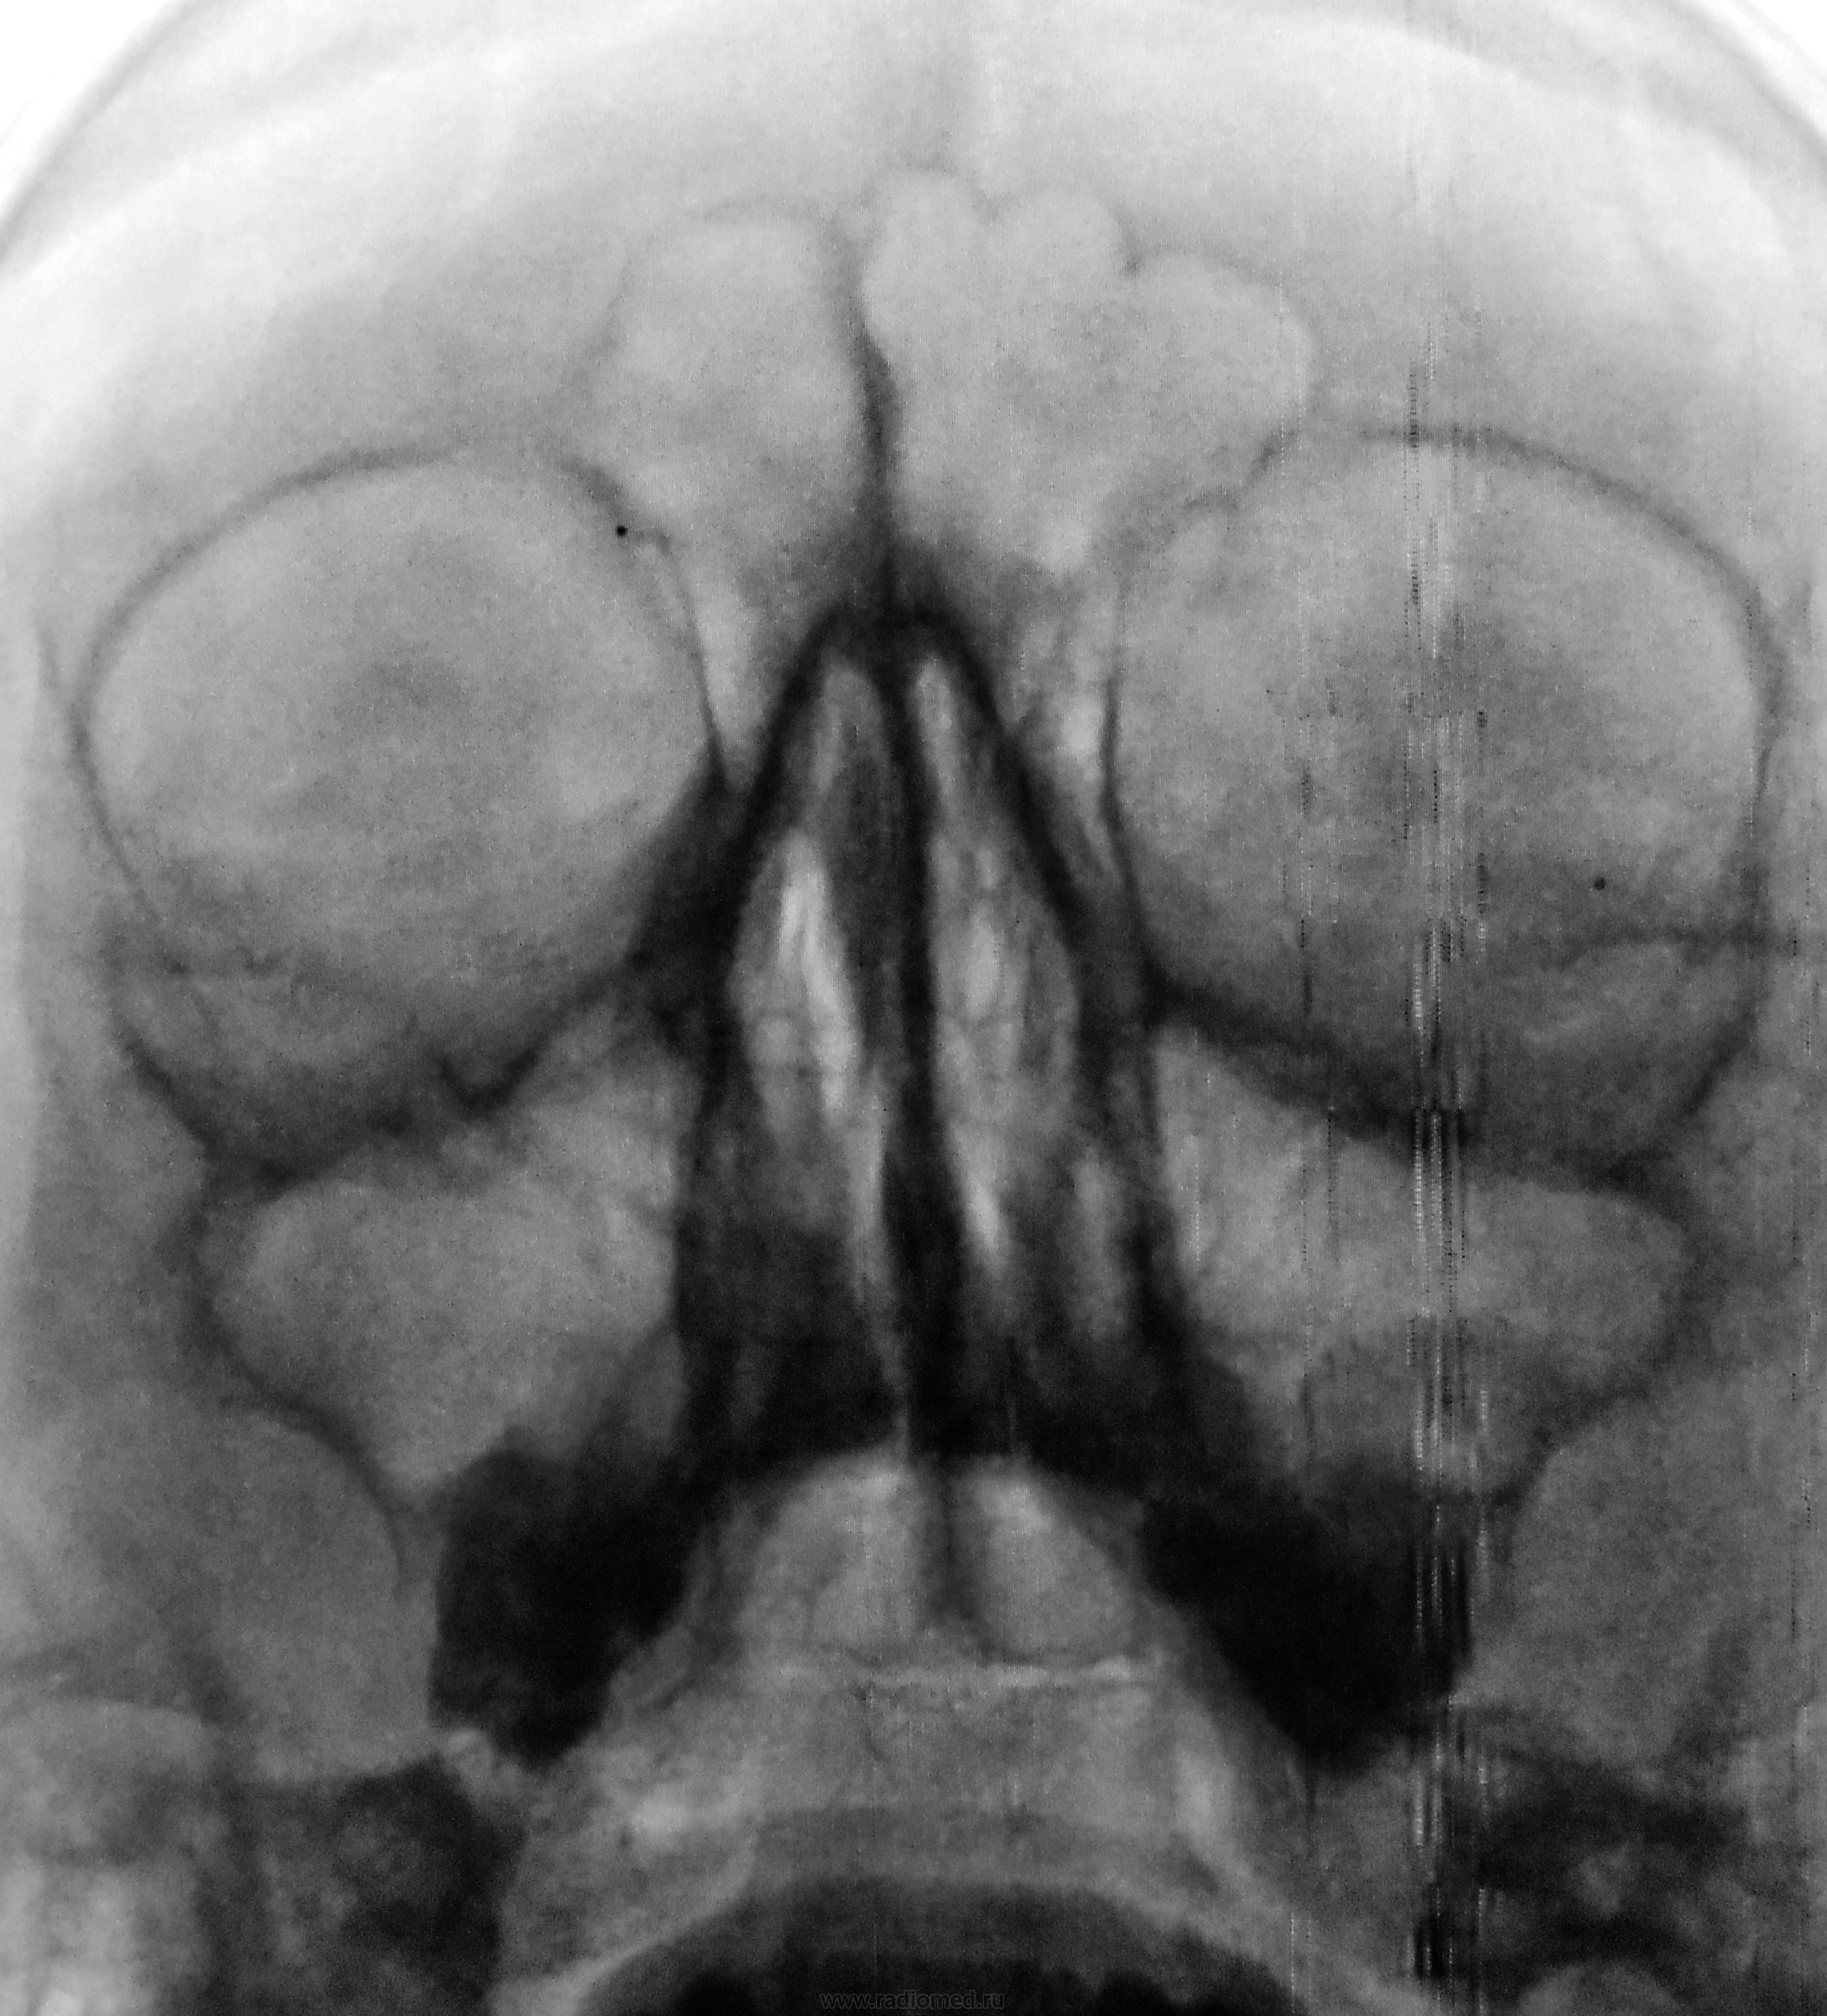

Пол пациента: Мужской пол Тип патологии: Другое Область исследования: Челюстно-лицевая область и шея Методы исследования: Rg Направлен на рентгенографию ППН с диагнозом хронический гайморит. https://radiomed.ru/sites/default/files/styles/case_slider_image/public/user/12/2.dscn0587.jpg?itok=udOrL36O https://radiomed.ru/sites/default/files/styles/case_slider_image/public/user/12/3.dscn0587a.jpg?itok=7Wzadi-t ID:24447 Wed, 14/11/2012 - 19:13 #1 Петр Николаевич Offline Last seen: 4 years 1 week ago Joined: 15.03.2011 - 13:22 Posts: 150 киста левой верхнечелюстной пазухи. Wed, 14/11/2012 - 19:29 #2 stovbav Offline Last seen: 2 years 5 months ago Joined: 20.12.2009 - 17:28 Posts: 7066 +1 Болезни ног: виды, симптомы, причины, профилактика и лечение Wed, 14/11/2012 - 22:56 #3 И.Бондаренко Offline Last seen: 7 hours 27 min ago Joined: 13.09.2011 - 22:55 Posts: 9208 Петр Николаевич wrote: киста левой верхнечелюстной пазухи. +1

киста левой верхнечелюстной пазухи.